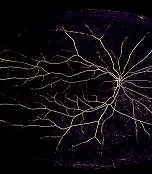

Imaging technology that scans blood vessels in the eye could be used to help diagnose a wide range of diseases, a study suggests. Software designed to assess the health of vessels in the retina could help scientists spot the early signs of heart disease, diabetes and dementia, researchers say. Changes to the retina are often a sign of sickness elsewhere in the body. The software - known as VAMPIRE - allows scientists to analyse the shape of blood vessels in thousands of images at a time and can identify known indicators of disease, the team says. VAMPIRE - which stands for Vessel Assessment and Measurement Platform for Images of the Retina - was developed jointly by scientists at the Universities of Edinburgh and Dundee. Researchers claim the software could save significant amounts of time by largely automating the process of looking for retinal abnormalities in large data sets. Image The team was the first to use a software tool to analyse images from more than 2,500 people who had retinal scans collected for UK Biobank, a long-term national health study. VAMPIRE proved effective at analysing images, though researchers say a larger trial is required to determine if it is the best way of utilising UK Biobank’s 80,000-strong retinal dataset. UK Biobank was established by the Wellcome Trust, Medical Research Council, Department of Health, Scottish Government and the Northwest Regional Development Agency. The study, published in the journal PLOS ONE, was supported by the Leverhulme Trust and the Edinburgh and Lothians Health Foundation Eye Research Fund. Dr Tom MacGillivray, of the University of Edinburgh’s Clinical Research Imaging Centre, who led the study, said: “This is the first step towards analysing all the retinal images held in the UK Biobank and to contribute valuable information about the health and condition of small blood vessels. Our work will hopefully accelerate research into the causes and treatments of chronic illnesses that affect millions of people in the UK.” Professor Emanuele Trucco, of the University of Dundee’s School of Computing, said: “The ultimate aim is to develop a practical software tool supporting efficient and accurate measurement and analysis of large collections of retinal images. The potential for research and clinical impact is huge." Related Links Eye imaging software could aid disease diagnosis Publication date 24 Sep, 2015